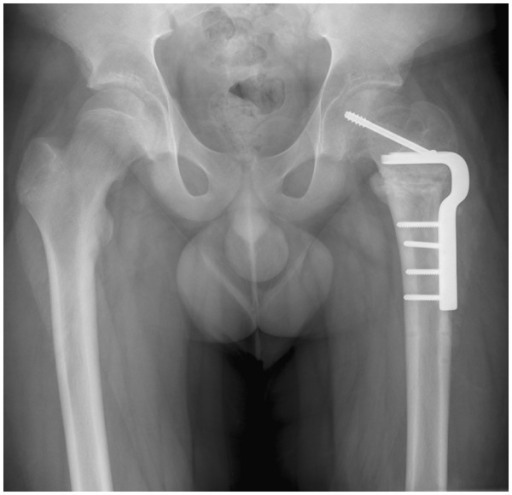

Epífisis femoral

Femoral epiphysis

La epífisis femoral es un área en el extremo del fémur separada de la parte principal del hueso por una placa epifisaria (placa de crecimiento).

A secondary bone-forming center of the femur, separated from the main part of the bone by cartilage during the period of bone immaturity.In overweight adolescents, there may be bone slippage along the femoral capital epiphysis, marked by pain and loss of range of motion.

We present our experience of the modified Dunn procedure in combination with a Ganz surgical dislocation of the hip to treat patients with severe slipped capital femoral epiphysis (SCFE). The aim was to prospectively investigate whether this technique is safe and reproducible.